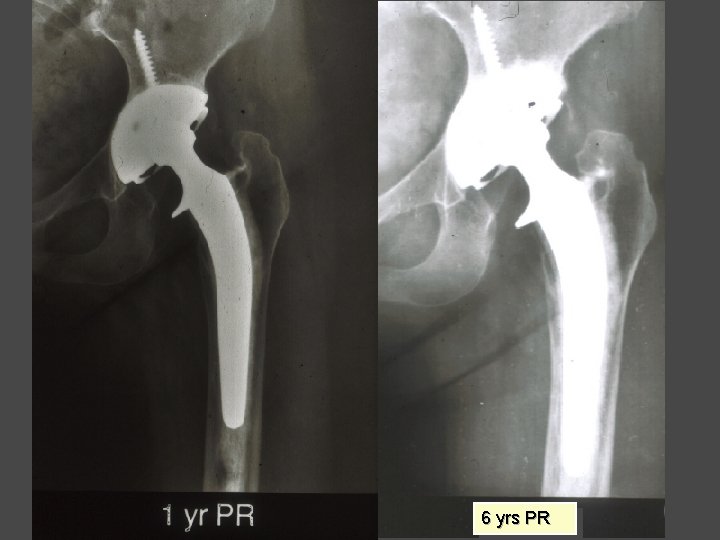

OSTEONECROSIS Cemented THA Results Yr No F-up Stauffer 82 Failure 10 yrs 8 yrs 50% Salvati 86 28 37% Kantor 96 28 7. 7 yrs 12. 5% Garino 97 123 6. 6 yrs 8%

OSTEONECROSIS Uncemented THA Results Yr Type No F-up Stem Socket (yrs) failure (%) Brinker 94 H-G 81 5 19. 7 6. 2 Lins 93 PCA 37 5 18. 9 2. 7 Piston 94 AML 35 7. 5 2. 9 5. 7 D’Antonio 97 HA-Omnifit 53 6 0 15

6 yrs PR